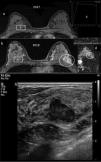

In the BRCA1 subgroup, annual screening with MRI and MG is less effective: larger BCs with more affected positive axillary lymph nodes and a higher rate of interval cancers are found.15,46–48 Also, the overall sensitivity of screening with MRI and MG is lower (some studies have cited figures of 81.3%15 or even 60%48) (Fig. 1). It seems clear that the interval must be shortened in this subgroup. In all other subgroups (BRCA2, history of chest radiotherapy and high familial risk), the screening strategy with annual MRI and MG is beneficial, with most tumours detected being T1a/b or DCIS and with a sensitivity of screening with MRI and MG ≥90%.15,47,49,50

A 32-year-old BRCA1 patient, in whom a new nodule was palpated in her left breast a year after her most recent magnetic resonance imaging (MRI) screening, before her next annual follow-up MRI. (A) Breast MRI with intravenous contrast: delayed 3D axial sequence with fat saturation from 2017 (a) and from 2018/time of diagnosis (b), where the 2018 MRI shows a new, oval-shaped, lobulated nodule in the upper outer quadrant of the left breast which washed out the contrast relative to the surrounding tissue in that delayed 3D axial sequence (circle). The contralateral breast (rectangle) shows a circumscribed prepectoral nodule with uniform internal enhancement, already known, with prior biopsy with a result of fibroadenoma, stable. Uptake curve for the nodule in the left breast, type 3, (c) and map of axial diffusion with apparent diffusion coefficient (ADC)=1.1×10−3mm2/s for the nodule (d). The nodule in the left breast was not visible on the 2017 MRI. (B) Breast ultrasound: lobulated, oval-shaped, hypoechoic solid nodule, with not completely circumscribed margins measuring nearly 3cm, underlying a palpable nodule in the left breast. An ultrasound-guided core-needle biopsy was performed with a result of “grade 3 infiltrating ductal carcinoma”. Molecular subtype: triple-negative. This was the only case of interval cancer at our centre to date in a BRCA1 patient.